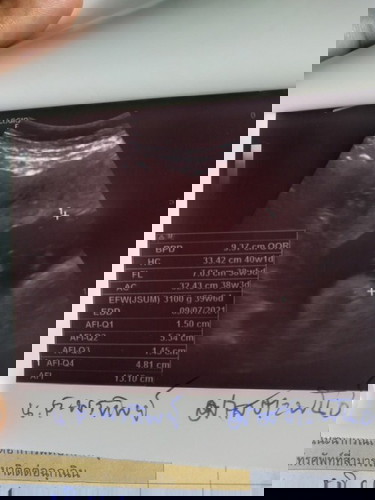

คือตอนนี้เราท้องได้39+5วีคแล้วมีอาการท้องปั้นบ่อยประมาณ3-4ครั้งต่อครึ่งชั่วโมงลูกดิ้นน้อยลงเรานับได้ตั้งแต่เช้ามาจนถึง18:40คือดิ้นแค่4ครั้งมีปวดท้องน้อยบ้างเป็นบ้างครั้งแล้วก็ปวดหลังอาการแบบนี้อันตรายไหมค่ะกลัวว่าลูกจะเป็นอะไรรึป่าวถึงดิ้นน้อยลง#ขอคำแนะนำหน่อยค่ะ #ขอบคุณล่วงหน้านะคะ #ขอบคุณสำหรับคำตอบค่ะ #ใครมีประสบการณ์